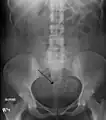

A very large (9 cm) fibroid of the uterus which is causing pelvic congestion syndrome as seen on CT

A small uterine fibroid seen within the wall of the myometrium on a cross-sectional ultrasound view- Two calcified fibroids (in the uterus)